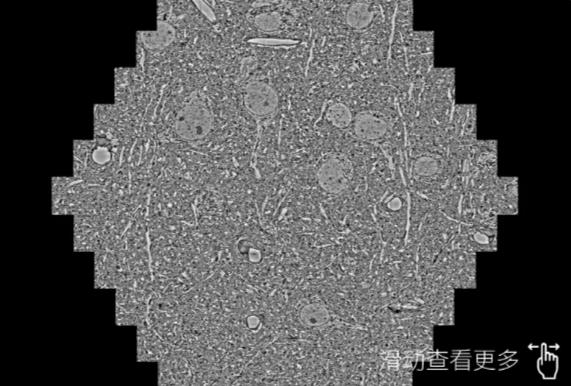

鼠脑切片。左图使用北辰蔡司北辰扫描电镜MultiSEM706对165μmx143pm面积区域成像,耗时仅需1.5秒。右图为鼠脑切片中30μm区域放大效果。样品由芝加哥大学B.Kasthuri提供。

使用蔡司高速北辰扫描电镜MultiSEM对1mm²人脑皮层组织进行高分辨成像,并对其中的各种细胞结构进行三维重构分析。左图展示了2x3mm²组织平面中锥体神经元的三维重构效果。右图显示了局部体积神经元三维重构。图像由哈佛大学chtman实验室提供,渲染图由D. Berger 制作。